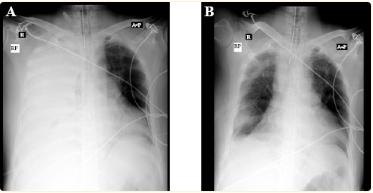

怀疑患者可能有胸腔积液复发,导致缺氧性停搏。在暂停胸部按压和插管期间,迅速进行胸部X光检查。令人惊讶的是,X线片提示右侧半胸完全混浊,并伴有肺塌陷(图1A)。因此怀疑这是张力性胸水导致的填塞效应。继续进行心肺复苏术,同时在右侧第5肋间隙行导管开胸术。

图1、病人的X光片。a:预插管胸腔造口术(患者仍处于心脏骤停状态);b组:胸腔造口术后引流尿液(ROSC实现)

放置28F肋间引流管,最初排出近4升液体,立即实现了自然循环(ROSC)的恢复。ROSC之后,X射线显示肺扩张和液体的部分清除,没有中线移位的证据(图1B)。排出的稻草色液体有一股可疑的刺鼻氨味。因此,考虑到可能是尿胸,发送了胸膜液进行肌酐检测。